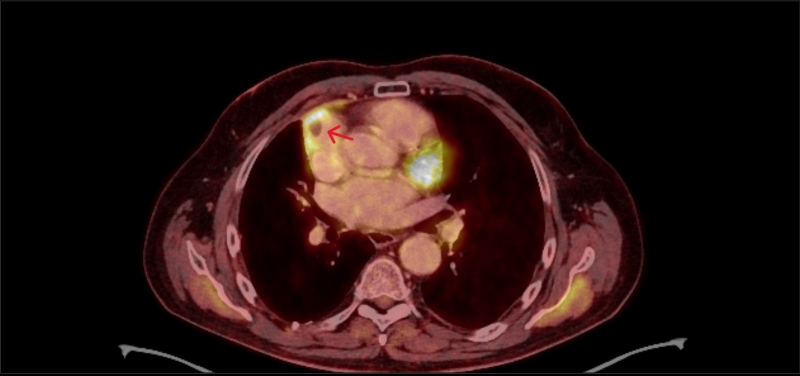

Suverénní diagnostickou metodou síňových trombů je jícnová echokardiografie. Alternativou je srdeční magnetická rezonance a CT, avšak právě výpočetní tomografie s sebou nese limitace ve formě nedostatečné distribuce kontrastní látky v oblastech krevní stázy. Následující kazuistika pojednává právě o nálezu izolované trombózy pravé aurikuly srdeční u pacienta po multimodální léčbě maligního mezoteliomu. Trombus byl diagnostikován jako vedlejší nález při PET/CT a následně potvrzen jícnovou echokardiografií.